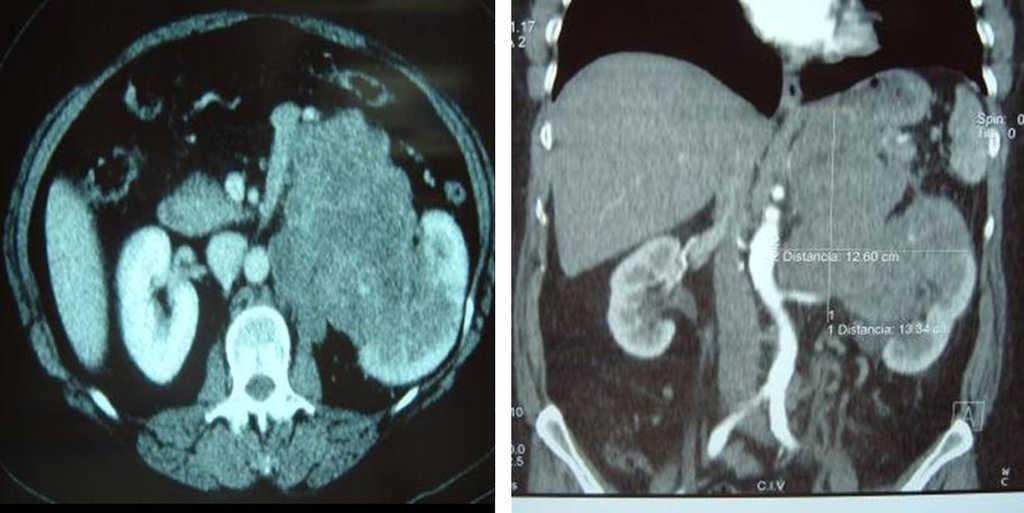

Presentamos el caso clínico de una mujer de 59 años con molestias abdominales difusas de 5 meses de evolución asociadas a anorexia y pérdida de peso de 12kg sin antecedentes médico-quirúrgicos de interés. En la exploración física se palpa una masa ocupante de espacio en el hemiabdomen izquierdo. Los estudios analíticos, que incluyen hemograma, bioquímica y pruebas de función hepática, son normales. La tomografía computarizada (TC) demuestra una masa retroperitoneal izquierda de contornos polilobulados y diámetros máximos de 13,8×10×14cm que infiltra el riñón y la glándula suprarrenal homolaterales, probablemente el fundus gástrico, el cuerpo pancreático y el pilar diafragmático izquierdo, y respeta la aorta abdominal (figura 1). Se realiza una laparotomía subcostal bilateral, en la que se objetiva una tumoración que afecta a la vena renal izquierda que infiltra riñón izquierdo, suprarrenal izquierda, cola del páncreas y ángulo esplénico colónico. Nuestra estrategia quirúrgica en los sarcomas retroperitoneales implica en primer lugar valorar la resecabilidad del tumor, lo que quiere decir que para obtener unos márgenes libres de enfermedad pueden ser necesarias resecciones amplias de órganos vecinos, y con un margen de seguridad intraoperatorio importante, es decir, tener en todo momento un control de las estructuras vasculares implicadas en dicha resección. De esta forma nuestra paciente fue sometida a una nefrectomía izquierda, suprarrenalectomía, pancreatectomía caudal, esplenectomía y hemicolectomía izquierda con anastomosis primaria, dejando clips metálicos sobre el lecho quirúrgico para facilitar una mejor localización en un posterior tratamiento radioterápico. El estudio anatomopatológico demostró un leiomiosarcoma de 13×10cm de diámetro máximo originado en la vena renal, con bordes bien definidos, de crecimiento expansivo y con extensas áreas de necrosis tumoral y hialinización. El tumor está formado por haces entrecruzados de células fusiformes, que demuestran un núcleo hipercromático, con marcado pleomorfismo y abundantes figuras de mitosis atípicas. El estudio inmunohistoquímico demuestra inmunopositividad de las células tumorales para vimentina, desmina, actina de músculo liso y actina específica de músculo e inmunonegatividad para citoqueratina, S-100 y C-Kit, con un índice de proliferación medido con el MiB1 muy alto. La paciente recibe tratamiento adyuvante con radioterapia (dosis de 45Gy) y tras un periodo de seguimiento de 17 meses se encuentra libre de enfermedad.

Figura 2. Tomografía computarizada abdominal. Gran masa retroperitoneal izquierda que infiltra el riñón y la glándula suprarrenal homolaterales, cuerpo pancreático y el pilar diafragmático izquierdo respetando la aorta abdominal.